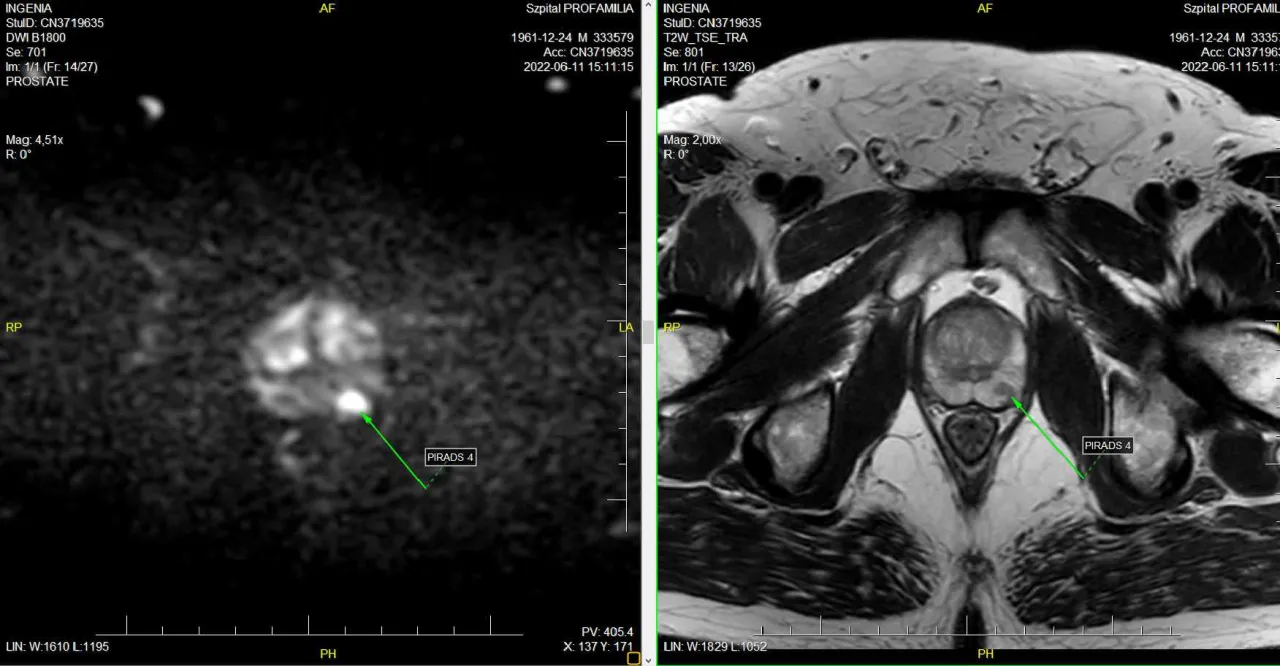

W ostatnich latach coraz większą rolę w kwalifikacji do biopsji odgrywa wieloparametryczny rezonans magnetyczny (mpMRI) prostaty. Badanie to pozwala na precyzyjną identyfikację podejrzanych zmian w prostacie, co znacząco zwiększa dokładność biopsji. Dzięki mpMRI lekarz może ocenić, które obszary gruczołu krokowego wymagają szczególnej uwagi, co przekłada się na bardziej celowane i efektywne pobieranie próbek.

Zupełnie innym podejściem jest biopsja fuzyjna, która jest uważana za najdokładniejszą i najnowocześniejszą metodę. Jej istota polega na cyfrowym nałożeniu (fuzji) obrazu z wcześniej wykonanego wieloparametrycznego rezonansu magnetycznego (mpMRI) na obraz USG w czasie rzeczywistym. Dzięki temu lekarz może z niezwykłą precyzją celować igłą biopsyjną bezpośrednio w podejrzane obszary, co znacząco zwiększa wykrywalność raka i ogranicza liczbę pobieranych próbek.